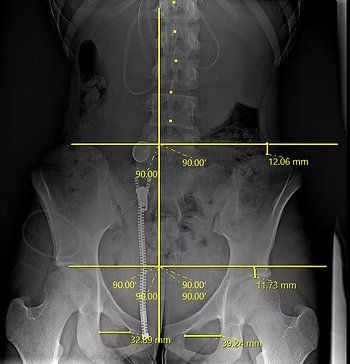

Here's an example of a younger person and an image of their low back and pelvis. This person has some aches and pains that have been bothersome for a couple of months. Here you can see the measurements between key points in the body. What we're looking for is an equal balance in the pelvis on both sides when we draw the top line straight across. Here you can see the right side is about 12 mm lower than the left. When we look at the middle horizontal line, the same thing is true with the femur heads, where the legs connect. We also draw a line vertically from the tailbone up along the spine to indicate the midline of the body. You can see there's a right tilt there with all of the vertebrae to the right of that midline. All of these things are important and oftentimes doctors don’t spend the time to go through this with you and explain how all of these pieces fit into the larger puzzle.

X-Ray of Pelvis Alignment